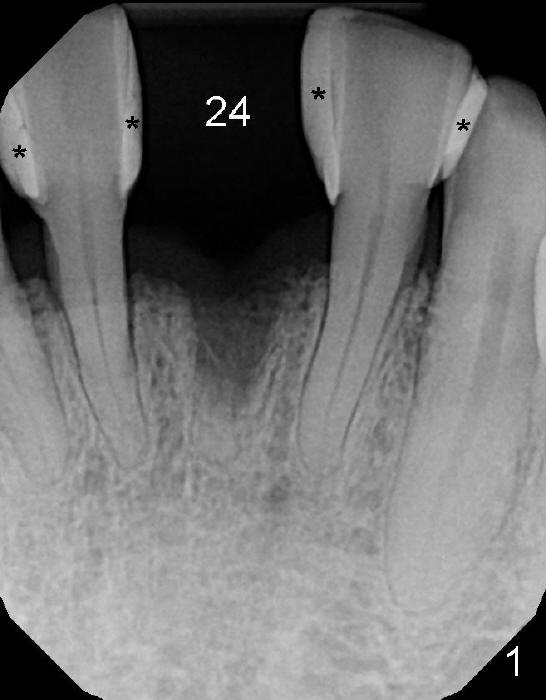

A 60-year-old man requests restoration of a missing lower central (Fig.1: #24).  His diabetes is controlled by med.  The edentulous space is wide mesiodistally; the diastemata between the adjacent teeth are closed by composite (*).  The tooth was extracted 2-3 years ago due to trauma.

To place the implant correctly, the preop PA should be studied carefully to find the divergence of the roots of the neighboring teeth (Fig.1).  The depth of the initial osteotomy should be shorter, for example, 11 mm instead of 14 mm.  Once the trajectory is found to be corrected, an incision should be made; the osteotomy is to be overcorrected with Lindermann bur (Fig.8 black); the whole osteotomy is changed with proper angulation (Fig.9 arrows).